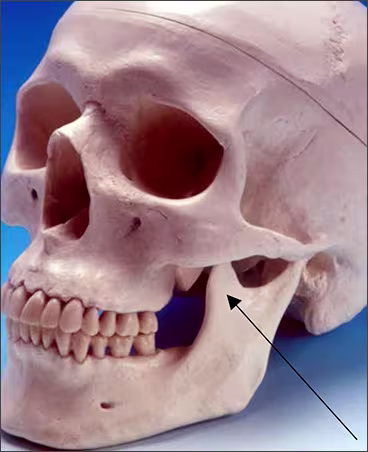

Coronoid process – The coronoid process of the mandible is the triangular bony portion of the anterosuperior aspect of the ramus. This mandibular structure can be recorded on maxillary molar periapical images as the ramus moves forward when the patient’s mouth is open. It appears as a bilateral triangular or thumb-like radiopacity on posterior maxillary images. The triangular portion projects forward toward the midline. The coronoid process is the only mandibular structure recorded on maxillary molar periapical images.